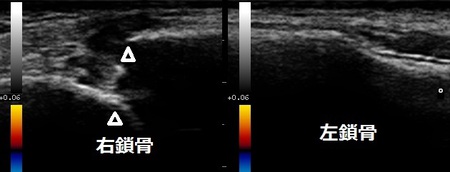

鶴ヶ島市 会社員 交通事故 鎖骨骨折

鶴ヶ島市 会社員 交通事故 鎖骨骨折。

1ヶ月前にオートバイ事故で転倒してしまいました。右鎖骨を骨折して、専用のバンド固定をしていました。

鎖骨がついたからと言うことで病院での治療は終了しましたが、まだ、右肩関節を動かしたときに鎖骨周囲に

痛みが残っています。

当院で超音波検査をしたところ、骨折部の間隙に仮骨が認められましたがまだ、骨硬化が強固な状態では

ありませんでした(左画像の矢頭の間の白い箇所)。

骨折部の骨硬化を促進させる治療機器を使用します。日常生活や仕事中はバンド固定を継続して、ゴルフなどの

スポーツは、定期的な超音波検査で骨硬化の状態を確認しながらスポーツ再開の時期を決めていきます。